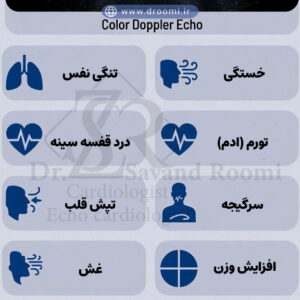

اینفوگرافیک هشداردهنده علائم بیماریهای دریچهای قلب که بر اهمیت تشخیص زودهنگام تأکید دارد.

علائم و نشانههای بیماری دریچه قلب که نیاز به اکو داپلر رنگی دارند

بسیاری از بیماریهای دریچه قلب در مراحل اولیه بدون علامت هستند، اما با پیشرفت، علائم مشخصی ظاهر میشوند که هشداردهندهاند. تشخیص زودهنگام با اکوکاردیوگرافی داپلر دریچه قلب میتواند از عوارض جدی مانند نارسایی قلبی جلوگیری کند. اگر هر یک از این علائم را تجربه میکنید، مراجعه به متخصص برای انجام اکو رنگی قلب برای دریچه میترال یا دیگر دریچهها ضروری است.

تنگی نفس، خستگی، تپش قلب و درد قفسه سینه

تنگی نفس، به ویژه هنگام فعالیت یا دراز کشیدن، یکی از شایعترین علائم نارسایی دریچه قلب است که ناشی از تجمع مایع در ریهها میباشد. خستگی مزمن و کاهش تحمل فعالیت نیز رایج است، زیرا قلب برای جبران مشکل دریچهای بیشتر کار میکند. تپش قلب (پالپیتاسیون) و درد قفسه سینه، شبیه به آنژین، میتواند در تنگی آئورت یا نارسایی شدید ظاهر شود. این علائم اغلب نیاز به ارزیابی فوری با اکو داپلر رنگی برای تنگی آئورت دارند تا شدت مشکل مشخص گردد.

سوفل قلبی و ادم

سوفل قلبی، صدایی غیرعادی که پزشک با گوشی پزشکی میشنود، نشانه کلاسیک مشکلات دریچهای است و اغلب اولین سرنخ برای درخواست اکوکاردیوگرافی میباشد. ادم (تورم) در پاها، مچ پا یا شکم نیز به دلیل احتباس مایع ناشی از نارسایی قلب رخ میدهد. در شیراز، بهترین متخصص اکوکاردیوگرافی دریچه قلب در کلینیک دکتر سوندرومی میتواند با استفاده از اکو داپلر رنگی این علائم را به مشکلات دقیق دریچهای مرتبط کند و برنامه درمانی مناسبی ارائه دهد.

تشخیص بهموقع این علائم با روشهای پیشرفته نه تنها درمان را آسانتر میکند، بلکه کیفیت زندگی را حفظ مینماید. اگر علائم مشابهی دارید، هرچه زودتر اقدام کنید.